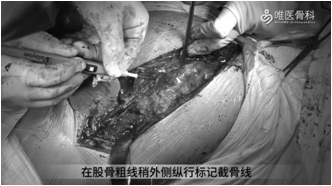

①给予向股骨远端延长切口,直至预计截骨处远端。显露股外侧肌后缘,在股骨粗线稍外侧纵行标记截骨线,验证远端截骨平面。

②用摆锯按照截骨线锯开股骨后方皮质,在预定平面横向分离侧方皮质。用骨刀穿透前侧皮质,并将截骨块向前方掀开,直视下清除残留骨水泥。